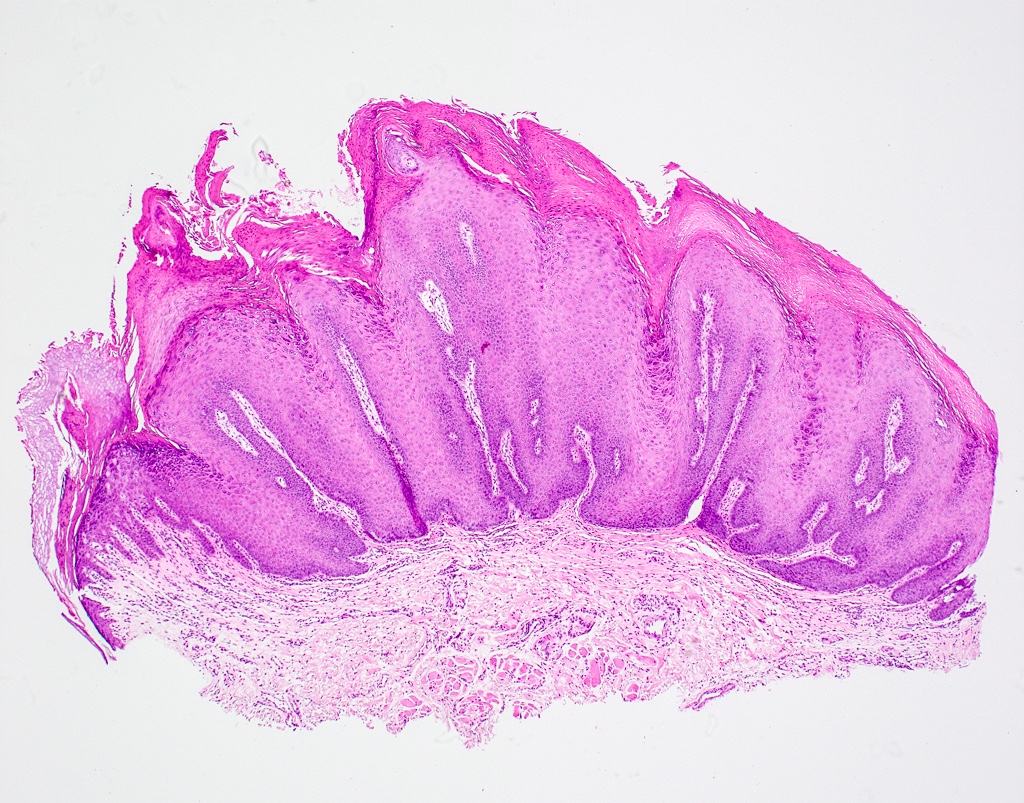

- Similar to cutaneous counterpart (Head Neck Pathol 2019;13:80)

- Prominent surface keratinization (often orthokeratin with superficial parakeratin tufts)

- Inward cupping of the rete pegs

- Exophytic / papillary fronds which form church spire-like peaks

- Hypergranulosis with coarse keratohyalin granules and potential eosinophilic intranuclear viral inclusions within the granular cell layer

- Koilocytosis within the superficial epithelial layers

Microscopic (histologic) images

C. Verruca vulgaris. The microscopic images show a well circumscribed, papillary epithelial proliferation with inward cupping of the rete ridges, prominent koilocytosis and prominent keratohyaline granules, which are all features of verruca vulgaris. Answers A and B are incorrect because condyloma acuminatum and squamous papilloma both lack prominent hypergranulosis while condyloma acuminatum exhibits broad, blunted papillary projections rather than the thin, hyperkeratotic projections seen above. Answer D is incorrect because verrucous carcinoma demonstrates broad, pushing rete ridges and lacks circumscription.